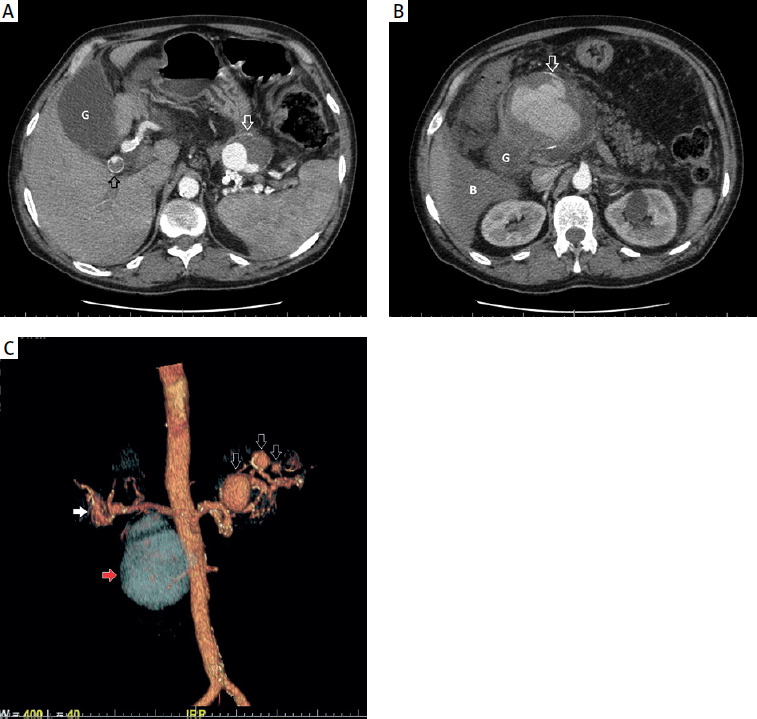

Figure 2

A – CT image after the applied treatment (angiographic phase, acquisition about 20 s after intravenous injection of contrast agent, intra-abdominal region) showing a large aneurysm, located along the course of the common hepatic artery, with no streaking of contrast into the sac (white arrow). The gallbladder is visible laterally (G). There is persistent fluid around the liver (B). B – CT image after treatment (angiographic phase, curved reconstruction along the common hepatic artery and hepatic artery) showing the implanted stent graft and the aneurysm located along the course of the common hepatic artery without contrast streaking into the pouch (A). Distally from the stent graft, an aneurysm with a small wall defect is visible along the course of the hepatic artery (white arrow). C – Arterial phase CT image – 3D reconstruction shows implanted stent graft (white arrow), aneurysm along the course of the common hepatic artery without contrast streaking into the sac (A). Along the course of the tortuous splenic artery, 2 aneurysms are visible (black arrows)